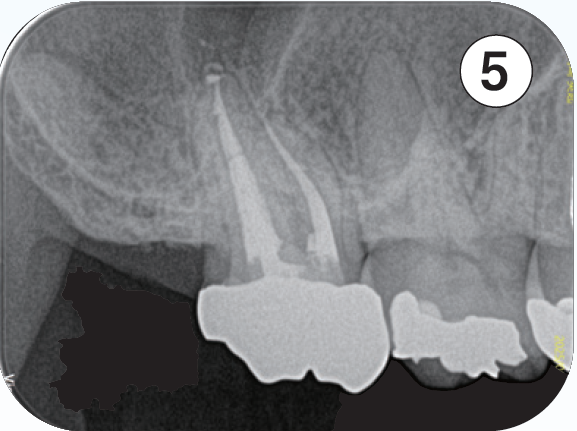

咬合による歯冠破折から歯髄炎になり、根管処置が必要となる。器具操作が困難なため、紹介を受け当院を受診。近心頬側根管は根管口付近は狭窄を呈し、遠心方向に向けて開口しており、近心頬側根管の器具の挿入はかなり遠心方向から器具を回し込む必要があった。また根尖の開口部は近心方向にあり、根管の全体的な形態はS字のような形態を有する。全体的に湾曲度を緩やかになるよう処置を進めた。器具の選択に関しては、より柔軟性のあるマルテンサイトのニッケルチタンファイルを選択した。根管口付近の形態修正は器具が歯軸に対して極力平行になるように行なった。EMR時のレントゲン像では、3根管それぞれが歯軸に対してほぼ平行に挿入されていることが確認できる。しかしながら根尖部付近がそれぞれ大小の湾曲を有し、特に近心頬側根は近心方向に湾曲している。根管上部の形態修正とマルテンサイトのファイルの使用によって根尖への器具の到達に成功した。根管充填はウォームドガッタパーチャとMTAシーラーを用いセクショナル法で行った。術後4年弱のレントゲン像で、根尖周囲の歯周組織は安定していることが確認できる。

① 初診時(2021/06/21)

口蓋根根尖部には炎症による歯根膜腔の拡大が見られる

②EMR測定時

根管口付近の修正形成を行い、ファイルが歯軸に対して平行に入ることによって根尖部の湾曲に対してニッケルチタンファイルがその特性を活かし、元々の根管形態を崩さず追従し根尖部への到達を獲得できている

③根管充填時

それぞれの根の根尖部に根管充填材が到達していることが確認できる

近心頬側根根管は根尖部は近心方向に湾曲して開口しているのが確認できる

④補綴装置装着時

根管処置後臨床症状もなくレントゲン所見も安定している

⑤術後4年弱(2025/05/28)

臨床症状もなく経過良好であり、初診時に見られた口蓋根根尖部の歯根膜腔の拡大も改善し安定している